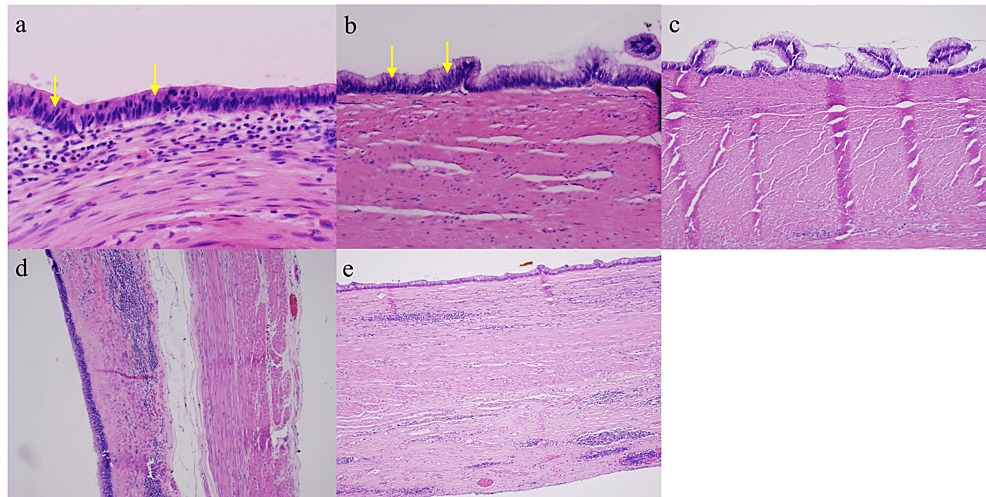

To evaluate for the development of PMP and metastasis and assess whether LAMN is present, a pathological examination is needed for further analysis. While frozen sections are sometimes obtained for diagnosis and resection margin analysis, they may not be helpful for diagnosis given the complexity of LAMN pathology and the limited correlation of frozen sections with the final pathology [9]. Pathologically, LAMN is characterized by atypical glandular cells, neoplastic mucinous epithelium, back-to-back crypts, sparse lamina propria, and extended villi (Figure 6) [1-2]. It grows outward via “pushing” invasion, creating dissected or tongue-like epithelium and diverticula [2]. Mucin and neoplastic epithelium may dissect through the muscularis propria and even breach the appendiceal wall, seeding into the peritoneum and progressing to PMP (Figure 7) [2]. However, there are no signs of “infiltrative” invasion such as budding, single-cell invasion, or desmoplastic stromal reaction [2].